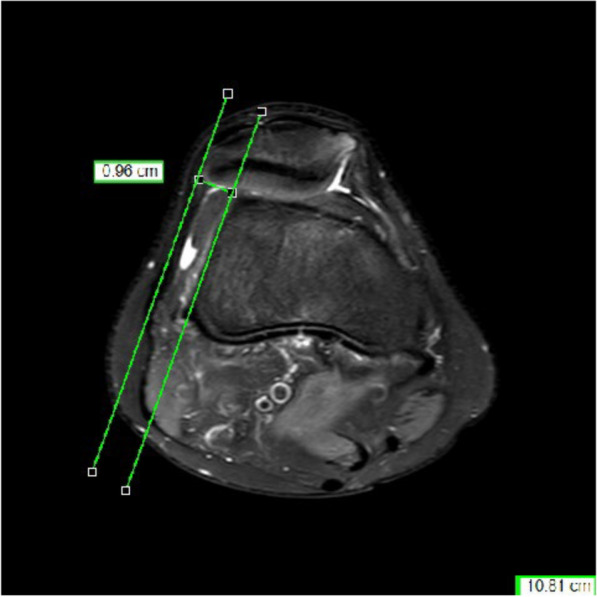

Methods: A total of 83 trochleoplasties in 83 patients were performed between 2014 and 2021 in one institution. Surgical indications for trochleoplasty were recurrent patellofemoral instability and a lateral trochlear inclination angle (LTI) ≤ 11˚ and a trochlear depth ≤ 6 mm. Of the trochleoplasties, 40 were done by open technique (OT) and 43 by arthroscopic technique (AT). In every case an additional medial patellofemoral ligament (MPFL) reconstruction was performed. Additional tuberosity tibia transfer and/or de-rotation of the femur were done when indicated. Pre- and postoperative magnetic resonance imaging (MRI) were analyzed in respect to LTI, trochlear depth, and lateralization of the patella. Postoperative subjective clinical assessment was done using the Kujala Score, Banff II Score, Tegner Score, and Marx Score.

Results: Of the patients, 15 with OT and 20 with AT were available for follow-up. The mean follow-up was 29.9 months in the OT group and 12.7 months in the AT group. No re-dislocation was observed in either groups. A significant reduction of LTI, increase of trochlear depth, and a reduction of lateralization of the patella was observed between the pre- and postoperative MRI scans in both groups. No significant difference in the observed MRI parameters was found between the two groups. Neither was there a difference in the postoperative Kujala Score, Banff II Score, Tegner Score, and Marx Score between the two groups. Length of stay was on average 6.2 days in the AT group and 8.1 days in the OT group. The surgical time was on average 141 min in the OT group and 160 min in the AT group.